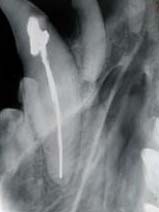

caso 1-RX-follow-up 60gg

Come si vede in questa proiezione RXdorsoventrale la frattura appare completamente guarita,inoltre è stato possibile riallineare i monconi di frattura in maniera accurata con il risultato di un’occlusione perfetta.